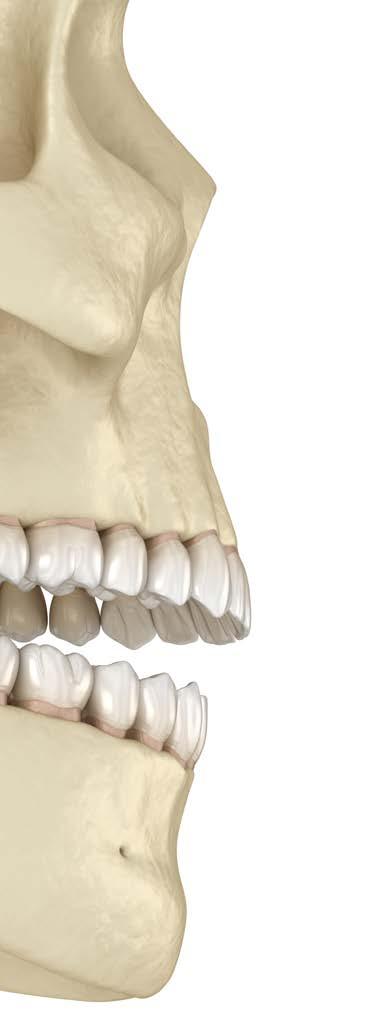

La disfunción de la articulación tem poromandibular, es el resultado de la evolución combinada de factores que, durante el crecimiento y desa rrollo craneodentofacial, genera inestabilidad en la relación, posición y dinámicas funcionales de los ele mentos anatómicos que conforman el universo estomatognático; es por tanto necesario que un diagnóstico temprano y el adecuado tratamiento interceptivo, armonicen y estabilicen las relaciones de posición y función del bloque óseo dental, junto con las biomecánicas adecuadas del comple jo neuromuscular. La relación cén trica ideal requiere de una oclusión céntrica óptima en cada caso, tanto en el paciente en desarrollo como en el adulto. Los factores ambientales, sociales, psicológicos, sumados a las alteraciones del desarrollo por enfer medades o aspectos congénitos, así como los ocasionados por la acción de una odontología deficiente, son detonantes que a corto, mediano y largo plazo se reflejan en la salud arti cular y oclusal del paciente. Lo que confiere la importancia de realizar acciones preventivas y correctivas durante el crecimiento y desarrollo y de tratamientos de rehabilitación adecuados para el adulto centrado en la estabilidad de posición, dinámi ca y función en la articulación tem poromandibular y en una máxima

intercuspidación acorde a las bases apicales y a la correcta estabilidad de las cargas en la oclusión.

Una detección temprana de altera ciones en el universo estomatogná tico, con la aplicación de maniobras adecuadas en base a un diagnóstico integral, evitará complicaciones en el desarrollo y funcionamiento adecuado a nivel articular y oclusal (Figura 1).

En la práctica odontológica cotidia na, se objetivisa resolver el motivo de consulta de nuestros pacientes de una manera rápida, en la que el factor estético sobresalga de todos los otros componentes que integran una reha bilitación por sencilla que esta sea. El panorama general del resto de los órganos dentales y su relación con la articulación, se desestiman, aislando exclusivamente la resolución por la que el paciente asiste a consulta. Es una constante identificar restaura ciones rodeadas de un sinnúmero de signos que están señalando proble mas que requieren de un tratamiento integral (Figura 2 y 3).